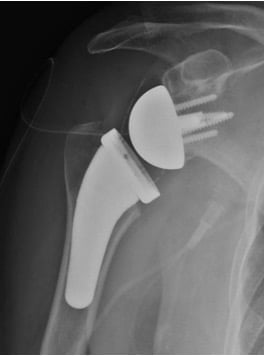

- Αρθροπλαστική: περιλαμβάνει την αντικατάσταση των φθαρμένων οστικών επιφανειών με μεταλλικές προθέσεις. Η αρθροπλαστική ενδείκνυται στις περιπτώσεις που η συντηρητική θεραπεία έχει αποτύχει και συμβάλλει στην ελαχιστοποίηση του πόνου και στην αύξηση του εύρους κίνησης του ώμου. Η επέμβαση πραγματοποιείται με συνδυασμό γενικής και περιοχικής αναισθησίας και απαιτεί συνήθως νοσηλεία μίας ημέρας. Υπάρχουν 2 κύριοι τύποι αρθροπλαστικής ώμου. Η Ανατομική Αρθροπλαστική Ώμου περιλαμβάνει την αντικατάσταση της κεφαλής του βραχιονίου με μεταλλική πρόθεση και την αντικατάσταση της ωμογλήνης με πλαστική πρόθεση. Η ανατομική αρθροπλαστική γίνεται σε νεότερους ασθενείς με ακέραιο στροφικό πέταλο. Η Ανάστροφη Αρθροπλαστική Ώμου πραγματοποιείται σε ασθενείς με σημαντικές ρήξεις στροφικού πετάλου και σε μεγαλύτερους σε ηλικία ασθενείς. Στην ανάστροφη αρθροπλαστική, η κεφαλή και η κοίλη επιφάνεια («κούπα») τοποθετούνται αντίστροφα από το φυσιολογικό (κοίλη επιφάνεια στην κεφαλή του βραχιονίου και γληνόσφαιρα στην ωμογλήνη). Η επέμβαση είναι πολύ επιτυχημένη και έχει γίνει εξαιρετικά δημοφιλής παγκοσμίως τα τελευταία χρόνια, με τα αποτελέσματα να είναι πολύ ενθαρρυντικά.